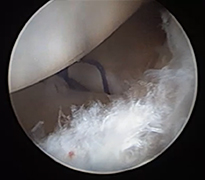

El bileği artroskopisi, el bileği ekleminin küçük kesilerden girilerek kamera ve özel cerrahi aletler yardımıyla değerlendirilmesi ve tedavi edilmesini sağlayan modern bir yöntemdir. Bu teknik sayesinde eklem içi yapılar detaylı şekilde görüntülenebilir. Özellikle bağ yaralanmaları, kıkırdak hasarları, TFCC (üçgen fibrokartilaj kompleks) lezyonları ve bazı kırık sonrası problemlerinin tanı ve tedavisinde kullanılır. Hastalar genellikle el bileğinde ağrı, hareket kısıtlılığı veya tıklama hissi ile başvurur.

Artroskopik yöntem, açık cerrahiye göre daha küçük kesilerle yapıldığı için doku hasarı daha azdır ve iyileşme süreci genellikle daha hızlıdır. İşlem sırasında hem tanı konulabilir hem de gerekli onarımlar aynı seansta gerçekleştirilebilir. Ameliyat sonrası kısa süreli istirahat ve ardından kontrollü egzersiz programı önerilir. Uygun hastalarda el bileği artroskopisi, ağrının azaltılması ve fonksiyonun geri kazanılması açısından etkili ve güvenilir bir tedavi seçeneğidir.